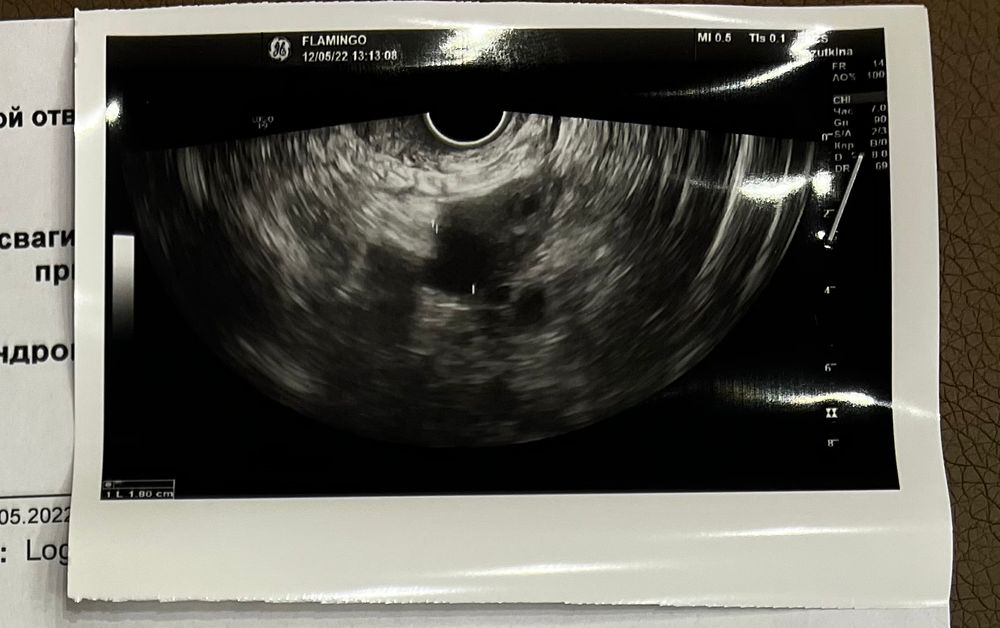

11 день цикла, 7 день стимуляции.

Была на узи. Фолликул растёт один, около 20 мм

Эндометрий тоже растёт.

А узист сказала, что фолликул натянутый, хороший.